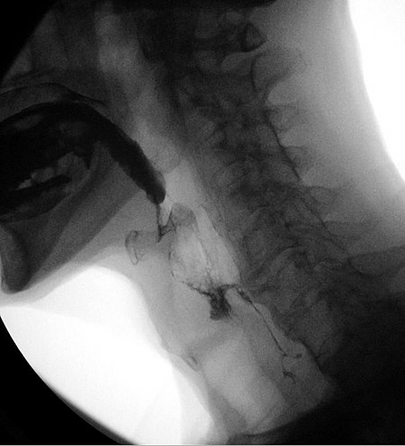

Videofluoroskopinis rijimo tyrimas (VFSS).

Videofluoroskopinis rijimo tyrimas (VFSS), dar vadinamas modifikuotu bario rijimu, yra dinaminis rentgeno tyrimas, kurio metu tiriama burnos ertmė, ryklė ir kaklo stemplė. VFSS leidžia įvertinti paciento rijimo funkciją suleidžiant įvairios konsistencijos skysčius ir kietąsias medžiagas, kad būtų galima fluoroskopiškai įvertinti rijimą.